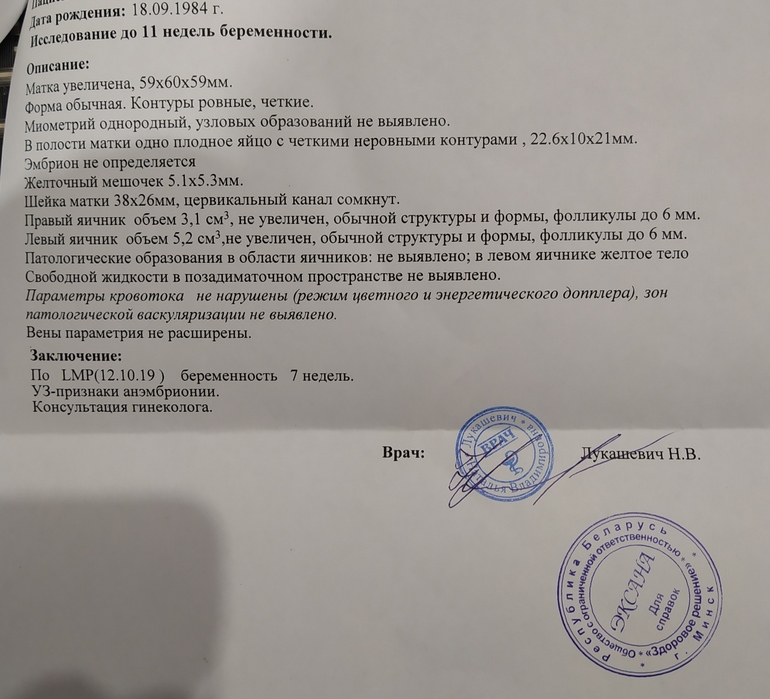

Со вчерашнего дня присутствуют коричневые выделения (именно коричневые, без крови, что очень хорошо) точнее сказать почти прозрачная жидкость, и в ней много коричневых прожилок. Вчера как то было совсем немного и я решила не вызывать скорую. Съездила утром на узи, чтоб успокоиться. Так вот на узи плодное яйцо 22,68 мм, желточный мешок 4 мм, но эмбриона так и нет. Срок у меня 6 недель 6 дней. К такому сроку он должен бы уже появиться. До этого был жуткий токсикоз, а сегодня нет. Врач сказала, что в нынешней обстановке ложиться на сохранение не самая лучшая идея. В голове много мыслей.. это вторая беременность, первая окончилась выкидышем. И сейчас мне очень страшно.